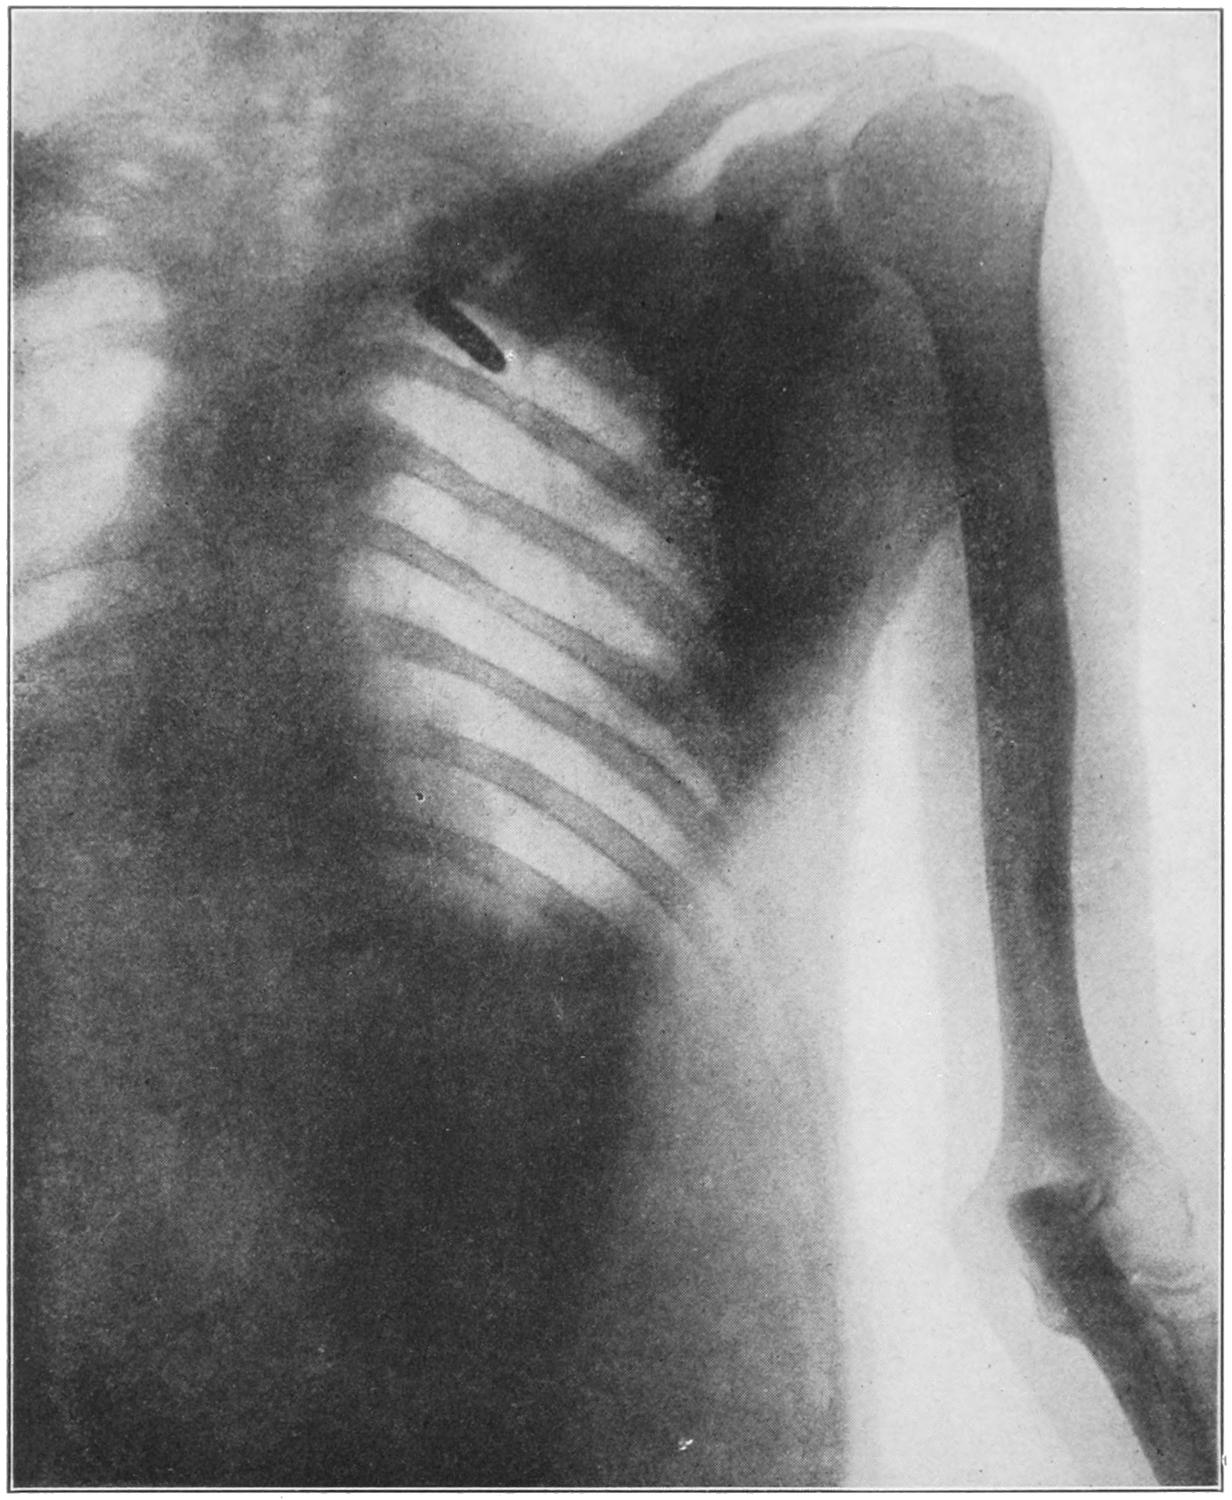

As a result of healing of the granulating surface there is what is known as a cicatrix or scar. This is composed of fibrous tissue, probably more or less distorted by virtue of its contractility, and of epithelial covering furnished from the margin of the original ulcer, constituting a thin, glistening membrane, applied closely to the scar tissue beneath, without intervening fat or tissue which permits of the play of the one upon the other. When this epithelial surface is abraded it is repaired with difficulty, and a raw or ulcerating[70] scar is difficult to heal. Manifestation of perverted epithelial outgrowth is frequently provoked at these points by the action of continuous irritation. In consequence there is what is generally recognized as the transformation of a chronic ulcer, or the site of one, into an epithelioma, or possibly, by similar irritation of the connective-tissue elements, into a sarcoma. This is the so-called cancerous degeneration of previous ulcers, and is noted occasionally. The lesion is one which often requires disfiguring, or even mutilating operations in order to get rid of the malignant disease (Fig. 12.) All the scars thus resulting are liable to undergo a fibrous and degenerative change to which is given the name cicatricial keloid. It is marked by increase in size and density, by reddening which denotes increased vascularity, and extension into surrounding previously healthy tissue. By these changes a given scar is made much more prominent and disfiguring. It cannot be prevented by any ordinary treatment, and is often the bête noir of surgeons. (See also under Fibroma, and chapter on Diseases of the Skin.)

The surface of a superficial scar while thus covered with epithelium shows a complete lack of all the other skin elements. No hair grows upon such a surface, because the original hair follicles are destroyed; neither is it moistened by perspiration nor anointed by sebaceous material, because the secretory glands have also disappeared. It is a surface which often needs more or less protection, especially when in exposed situations.

Treatment.